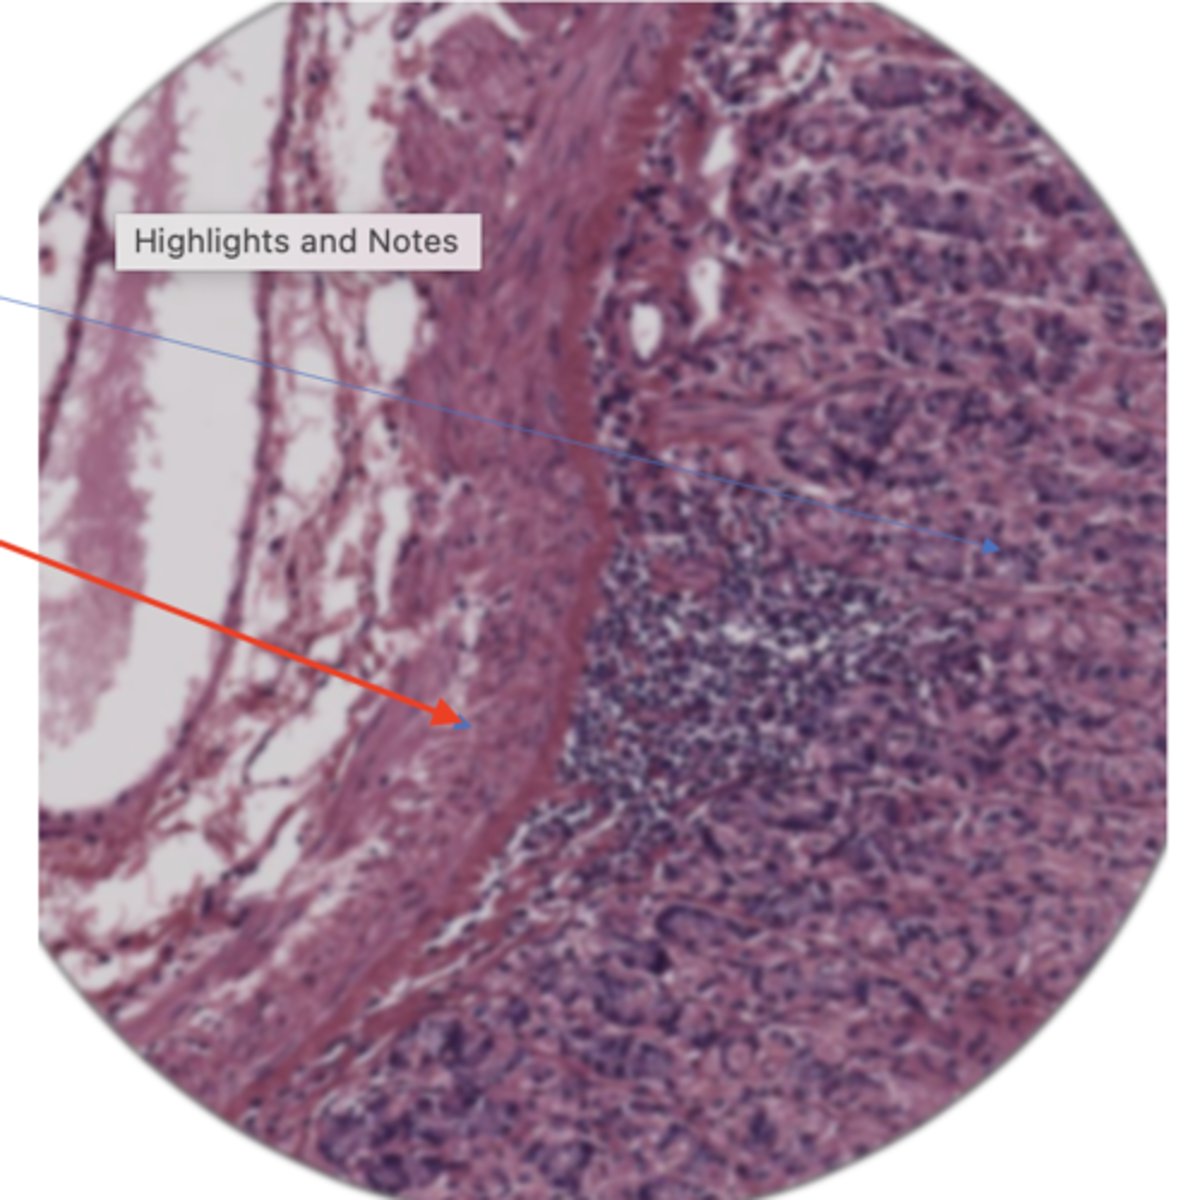

stomach mucosa layer (400)